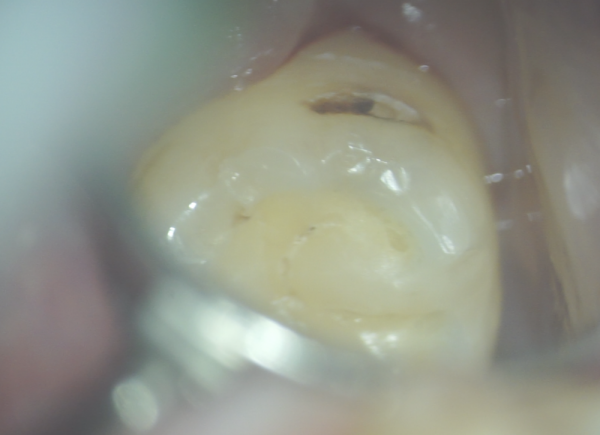

奥歯の虫歯

親知らずが原因で奥歯が虫歯になったケースです。

親知らずが原因で奥歯が虫歯になったケースです。

一番奥の裏側なのでミラーをうまく利用してマイクロスコープがあるからなんとか視認できています。

ここには普通の道具では届かないので、歯科の中でも特殊な2回湾曲した超音波チップを使用して虫歯を削っていきます。